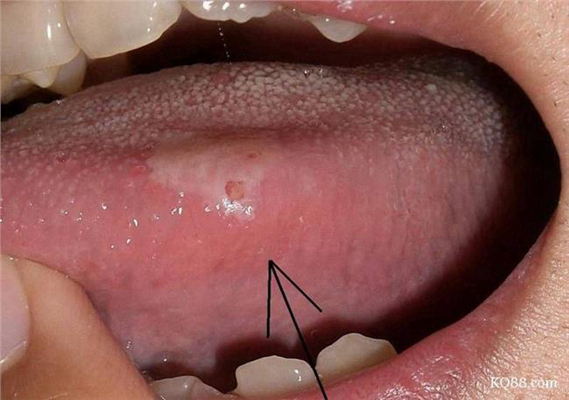

A:舌癌一般是在舌側緣出現腫物,有外生型、潰瘍型和浸潤型。最常見的是外生型和潰瘍型,一般在早期就是在舌側緣出現一個深的潰瘍,而且潰瘍長期不愈。和普通的口腔潰瘍不同,舌癌的潰瘍兩個月以上也不會自行癒合,創面不斷的增大、加深,加深到一定程度舌頭會出……

A:吃辣的舌頭疼應該不是舌癌,辣不是種味道而是種燒灼感,所以吃辣的出現舌頭疼是正常現象,也就是辣椒素刺激了舌黏膜引起疼痛感。舌癌不是這樣的表現,舌癌發生在舌側緣,有外生型也有潰瘍型。外生型的是向表面突出,表面黏膜不是光滑、完整的,有的是呈菜花樣……

A:判斷是否得舌癌的唯一標準就是就診進行病理檢查,就是在舌體的病變部位取一塊組織進行病理分析,這個是可以確診的手段。如果確定得了舌癌,一定要及時的採取手術治療,切除乾淨,必要時還要進行淋巴結清掃術,減少擴散的可能性。術後必要時還要配合放療和化療……